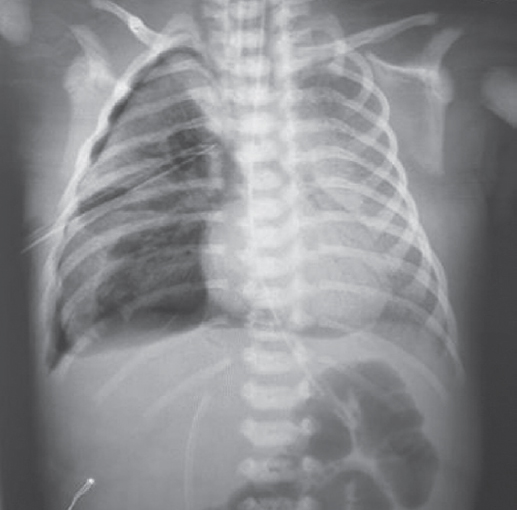

На контрольной рентгенограмме, выполненной на вторые сутки жизни (после введения сурфактанта), сохраняются признаки тяжелого РДС, осложнившегося правосторонним напряженным пневмотораксом (рис. 2), в связи с чем по экстренным показаниям было выполнено дренирование плевральной полости.

Рис. 2. Рентгенограмма органов грудной клетки новорожденного после введения сурфактанта

Fig. 2. Chest X-ray of newborn after surfactant administration